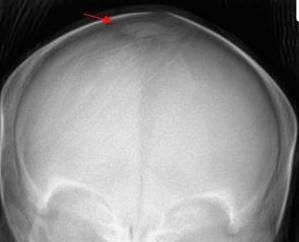

In the newborn nursery, an abnormality of the cranium of a full-term, 39-week gestational-age boy was noted on palpation. The infant was found to have a wormian bone.

Courtesy of Emily Osier, MD, Susan Bacsik, DO, Gregory Jackson, MD, Laura McClendon, MD, Dorothy Sendelbach, MD, and Elizabeth Kaili Stehel, MD